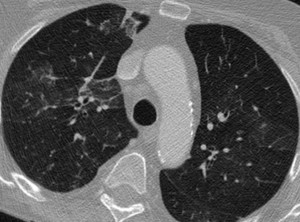

Para diagnosticar esta enfermedad, por lo general se requiere que al paciente se le haga una radiografía de tórax acompañada de una exploración física, basado en esto se establece su severidad y el tipo de neumonía, para así comenzar a proceder en el tratamiento adecuado; no todos los casos requieren que el paciente sea internado en un hospital, esto se da en los casos más graves y severos o en otras circunstancias también dependiendo de la condición social en la que se encuentre.